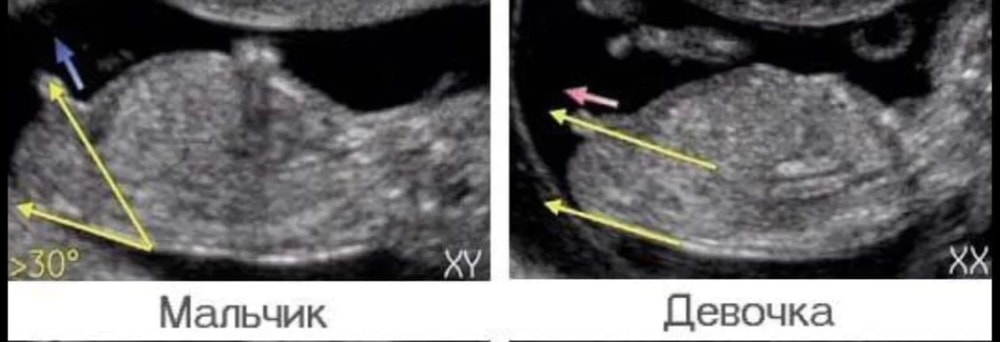

Лучше фото увы нет. 11-13 недель. Была у двух узистов. Один поставил 11.2, другой 12.6, акушерский 13.5. Сама понимаю, что скорее всего не понятно там вообще 🤣 Но видела что тут и по более худшим фото гадают. ЧСС 161

Девчонки, исправляю. Вы угадали. Действительно девочка)